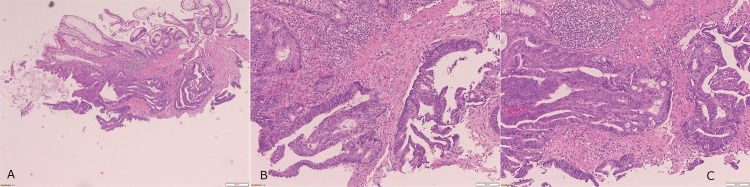

病理检查显示高级别异型增生腺上皮,腺体结构紊乱伴固有层浅表浸润,提示为高分化腺癌(图2)。未见淋巴血管侵犯或神经周围肿瘤浸润。免疫组织化学检测显示MLH-1与PMS-2表达保留,MSH2与MSH6表达缺失,提示错配修复缺陷状态。分子检测检出KRAS G12D突变,BRAF、NRAS、PIK3CA、PTEN及AKT1均未见突变(图3)。

图2. 组织切片 H&E 染色结果,(A) 4倍镜视野,(B、C) 10倍镜视野